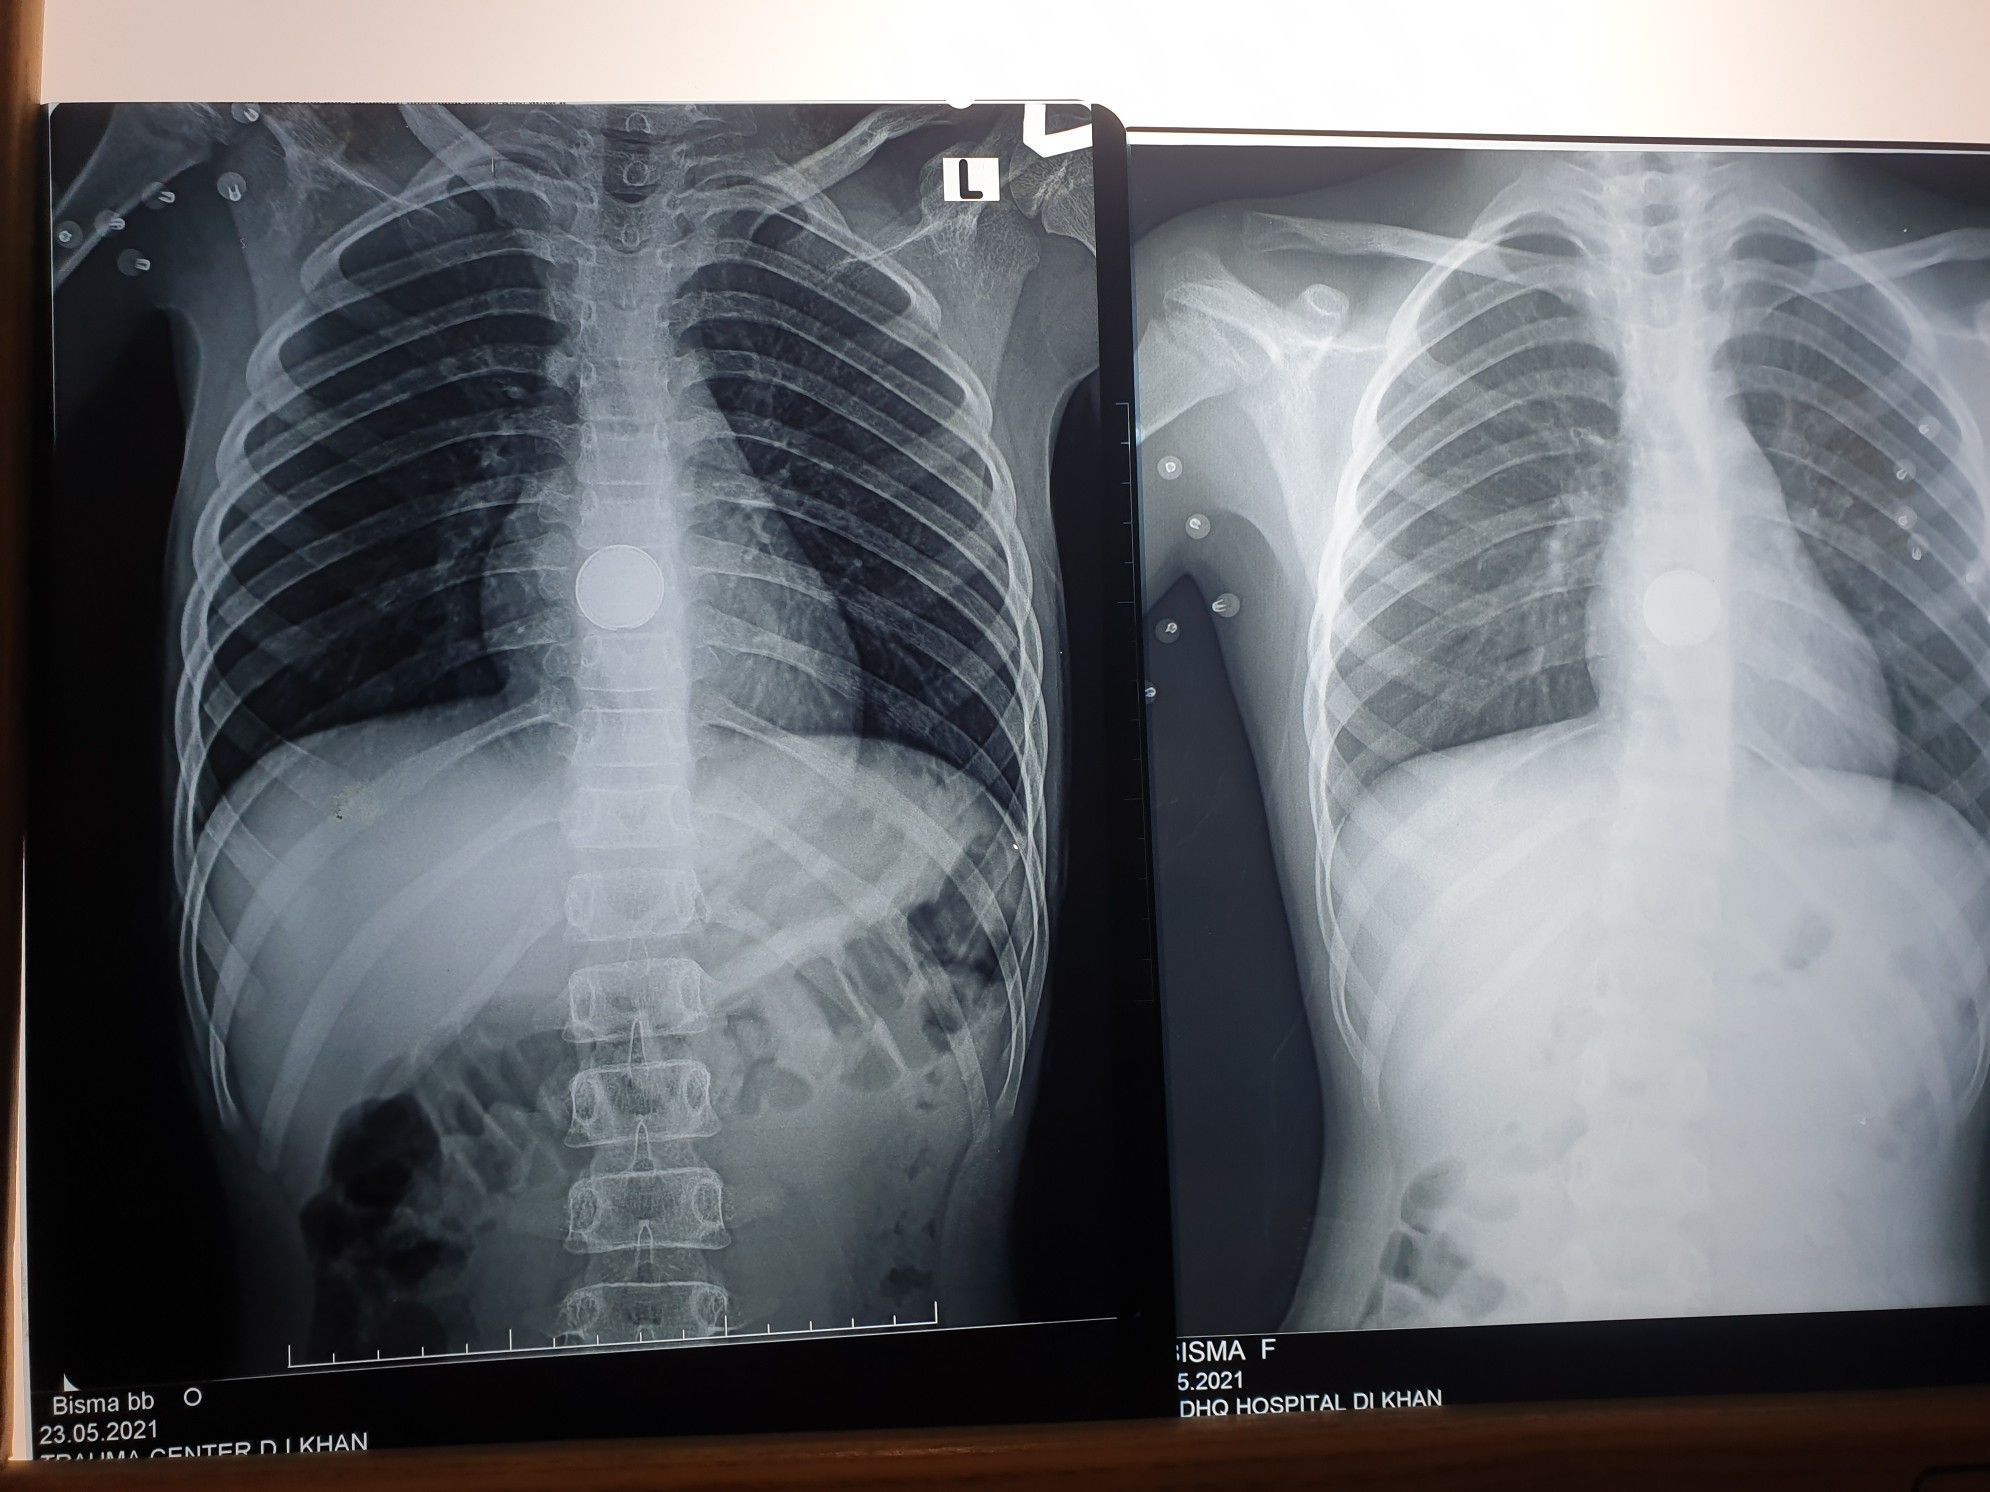

Interesting case Patient 9yo was received to ENT ward through call from peads ward. Pateint was having complaints of chest pain and foreign body ingestion. According to the patients attendant she ingested a coin unintentionally. So the patient was kept under observation as a coin would usually go into faeces. But today was 4th day of admission and CXR showed coin still stuck at the same place. Our doctors became doubtfull and recalled the pateints attendant. Our doctors were thinking it might be a cell(battery) mistaken by a coin. So further questioning revealed it was a cell from a calculator. We got alert and asked the patient to be shifted to OT as the cell is very dangerous and might have caused alkali reaction. Pateint was given general anesthesia and prepared for oesophagoscopy. Oesophagoscopy revealed significant granulation tissue, fresh wound, sloughed mucosa but no deep ulcers found. The coin/cell was not seen and findings were noted. And patient is sent to repeat CXR as the cell might have been dislodged . Now further workup is to be planned after the CXR. But today i saw the importance of history and how a wrong history could lead to terrific misled diagnosis and treatment. If a day or two late, the cell would have caused perforation and it would have been really challenging to treat the complications.